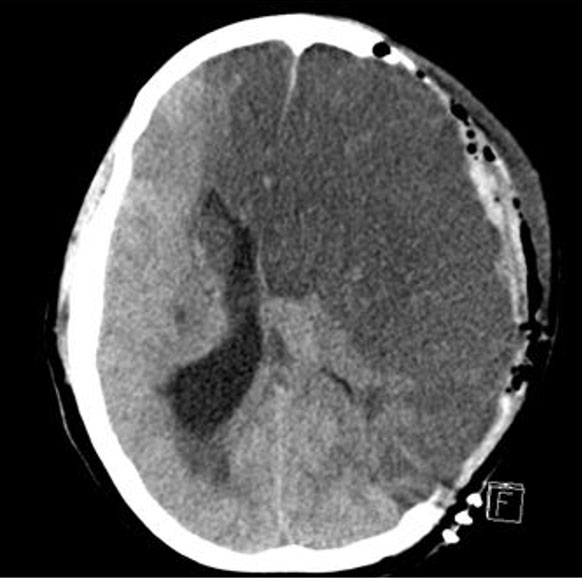

Her exam worsened and was significant for bilateral fixed and dilated pupils. Stat head CT showed a 9 mm midline shift of the left hemisphere (Figure 3). She was taken for emergency, decompressive left hemicraniectomy and intracerebral pressure monitor placement. Imaging from postpartum day 4, postoperative day 1 was significant for a devastating left hemispheric infarct.

Figure 3: CT imaging from postpartum day 4, postoperative day 1 from decompressive left hemicraniectomy and intracerebral pressure monitor placement. Significant for a devastating left hemispheric infarct.